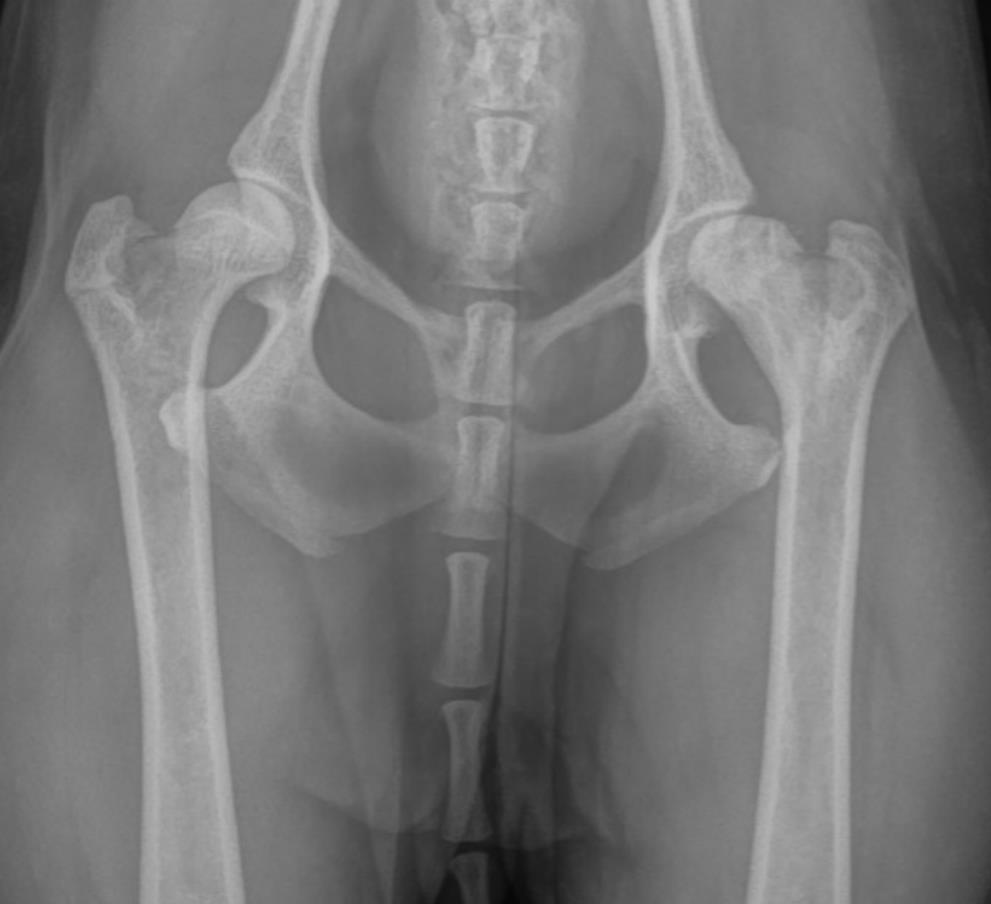

The patient presented for left hindlimb lameness which was localized to the left hip. Radiographs were most consistent with a diagnosis of Legg–Calvé–Perthes disease. The patient underwent a femoral head osteotomy, and the tissue was submitted for histopathology.Gross Pathology:

IMAGE ONLY WITH CAPTION - Pre-operative VD radiograph of the hips showing bone loss, osteolysis and a severely misshapen left femoral head.Microscopic Description:

The signalment, clinical history, radiographic findings and histopathology are most consistent with a diagnosis of avascular necrosis of the femoral head, also known as Legg-Calvé-Perthes Disease or Osteonecrosis of the femoral head.Avascular necrosis of the femoral head (ANFH) is a well-recognized condition which occurs most frequently in small breed dogs, including miniature poodles, West Highland White terriers and Yorkshire terriers.3 This condition is heritable in these breeds and there is evidence to support an autosomal recessive mode of inheritance.2,3 Most affected individuals present between 3 and 13 months of age with unilateral hindlimb lameness.2 The condition is bilateral in approximately 12-17% of cases.2 A significant percentage of dogs have concurrent patellar luxation which can complicate diagnosis, particularly as radiography lacks sensitivity in detecting early cases.2,7

The gross and microscopic pathology varies depending on the chronicity of the disease at the time of diagnosis.1,3 Early on, the shape and structure of the femoral head are grossly and radiographically normal. Histologically, there may be evidence of osteonecrosis predominantly within the subchondral bone at this stage.1 With chronicity, if the area of necrosis is large enough, the necrotic bone collapses which causes flattening of the femoral head (Figure 1) which eventually results in a degenerative arthropathy.1,3